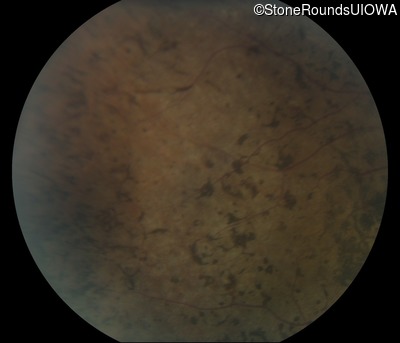

Fundus Photography - Right - Light Perception

Exemplar

Fundus Photography - Left - Light Perception